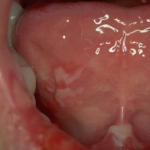

Pemphigis Vulgaris =الفقاع الشائع